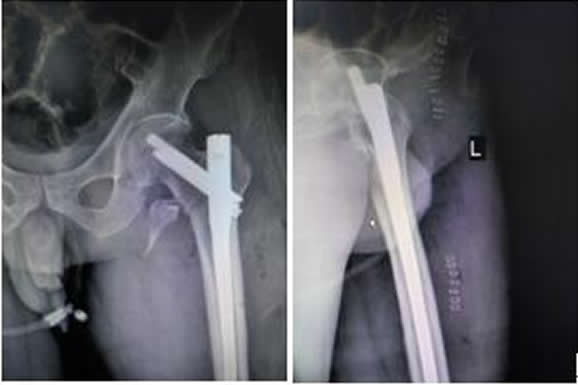

患者劉某某,男,70歲,以“左髖摔傷疼痛活動受限2小時余”之主訴于2016.9.26入院。入院診斷:左股骨近端粉碎骨折?;颊哂?016.9.30上午硬腰聯(lián)合麻醉下行骨折閉合復位InterTan內固定術。手術順利,術后患者恢復良好,現(xiàn)已出院。術后復查拍片如下:

左髖關節(jié)正側位X線片